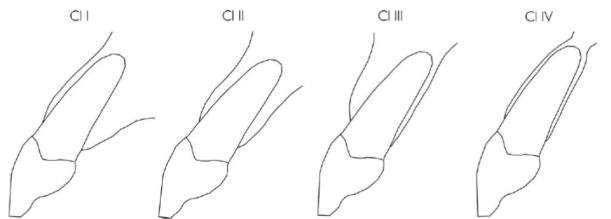

Kan’s

- Class I:牙根靠著唇側的cortical plate,最常見

- Class II:牙根位於唇舌徑的中間且根尖1/3沒有碰到任一邊的cortical plate。

- Class III:牙根靠著顎側的cortical plate

- Class IV:至少2/3的牙根有同時接觸兩側的cortical plate

過去即拔即種在顎側骨,所以 Class I 最多 (因為沒有那麼長的質體)